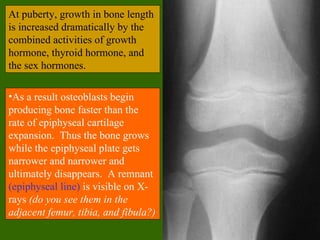

At puberty, growth in bone length

•As a result osteoblasts begin

producing bone faster than the

rate of epiphyseal cartilage

expansion. Thus the bone grows

while the epiphyseal plate gets

narrower and narrower and

ultimately disappears. A remnant

(epiphyseal line) is visible on X-

rays (do you see them in the

adjacent femur, tibia, and fibula?)